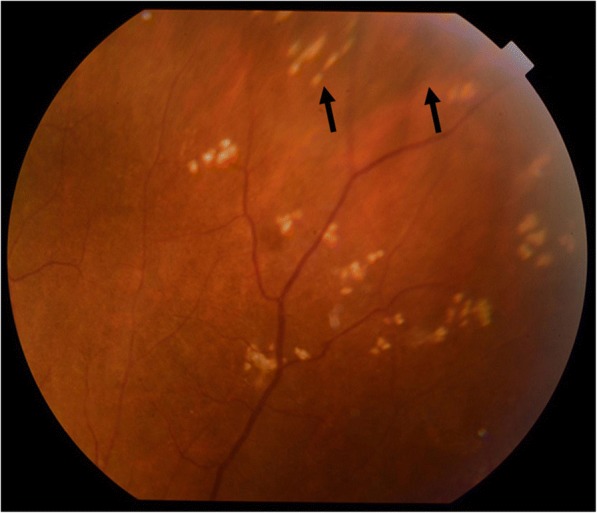

Fig. 3.

Fundus photographs obtained when scleritis relapsed, accompanied with an intraocular elevated lesion. a Intraocular elevated lesion at the superior nasal retina (arrows). b Enlarged photograph of the intraocular elevated lesion (arrows)

In regard to the follow-up treatment course, we initially increased the frequency of the instillation of steroid eye drops and added immunosuppressive eye drops. However, those drugs were ineffective, and the vitreous opacity gradually increased. Thus, we increased the amount of oral prednisolone to 20 mg per day in November 2014. Subsequently, the eye redness and vitreous opacity gradually disappeared within approximately 2 weeks, her VA slowly improved, and there was no remarkable fundus abnormality in the right eye at each examination. However, uveitis accompanied with moderate ocular pain relapsed (Fig. 2a, b), and fundoscopic examination revealed an intraocular elevated whitish lesion at the superior nasal retina of her right eye in November 2015 (Fig. 3a, b). We did not observe any restricted motility accompanied with eye movement. B-scan ultrasonography was also performed, and revealed that the sclera was thickened and that the lesion seemed to have high internal reflectivity (Fig. 4). Although the patient underwent a magnetic resonance imaging (MRI) scan for a differential diagnosis, it was difficult to distinguish whether the lesion was a granuloma or a tumor. Ultrasound biomicroscopy (UBM) and high frequency B scan might have been useful to distinguish between a tumor and granuloma, however, those examinations were not available at that time.